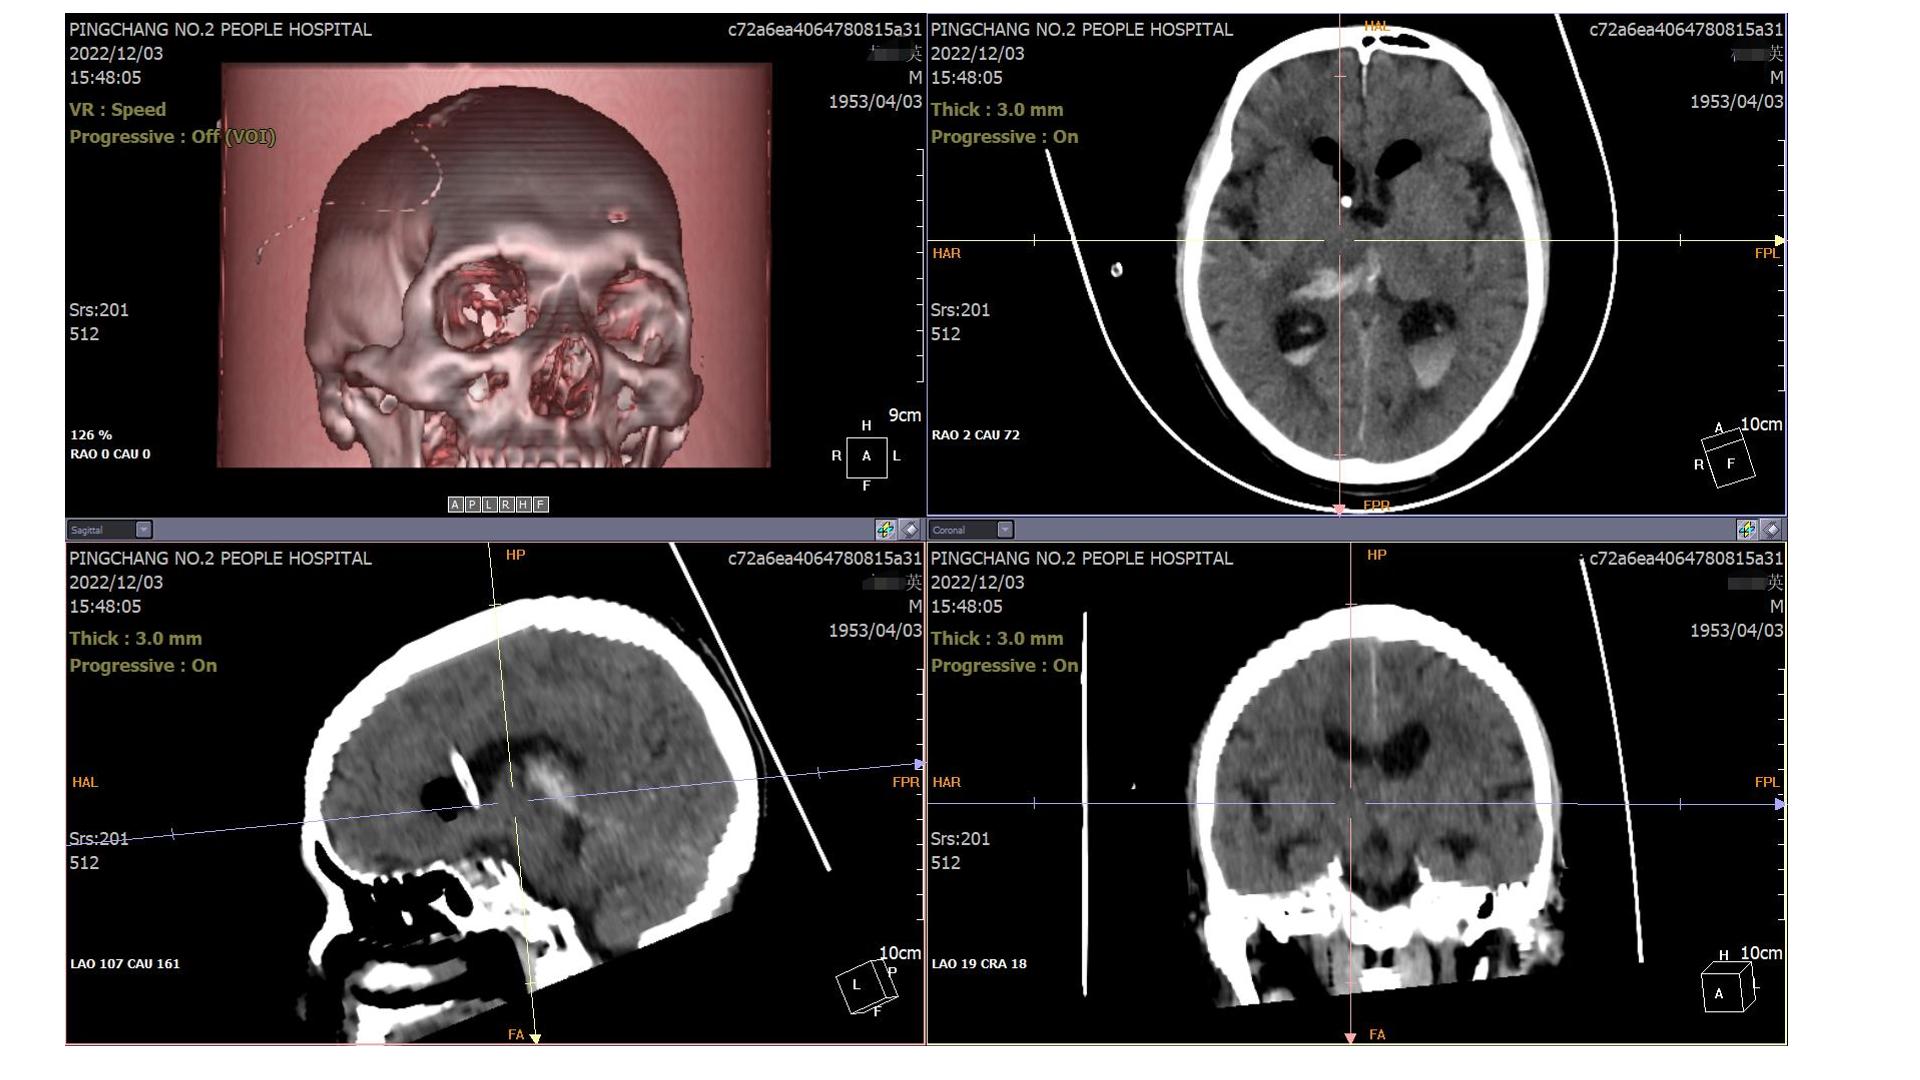

2022.12.03